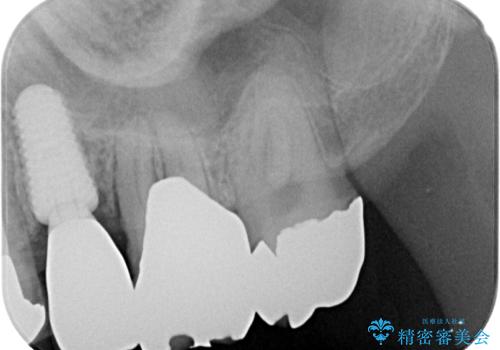

抜歯と同日にインプラントを埋入し、さらに仮歯まで装着するため、治療当日から見た目と噛む機能の回復が可能です。治療期間中も審美性と日常生活の快適さを維持できます。

抜歯即時インプラント後、治癒期間を経て、約3か月でセラミックによる最終補綴が完了しました。